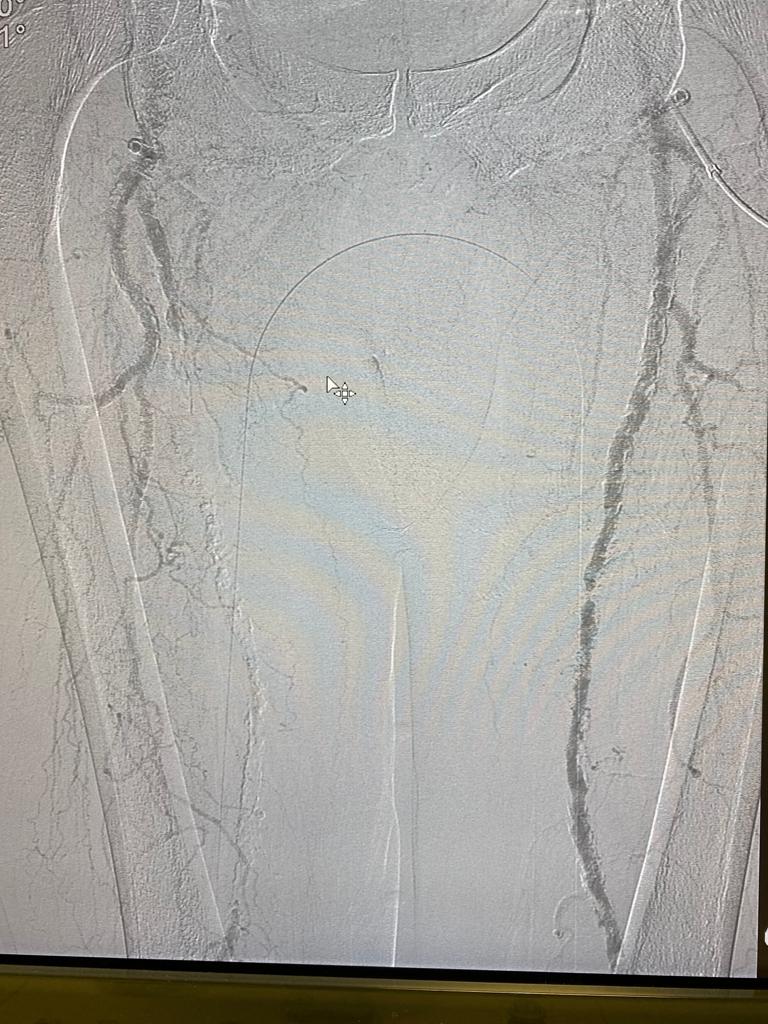

El paciente carecía de pulsos distales y en este caso ya que no existía una infección severa optamos por realizar una revascularización del paciente y durante ese periodo estuvo cubierto con antibióticos dirigidos mediante biopsia ósea mientras se realizaba la revascularización.